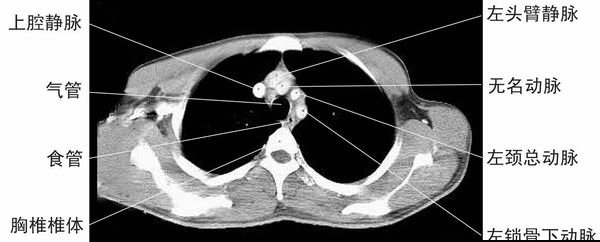

主动脉弓上层面-胸部CT断层影像